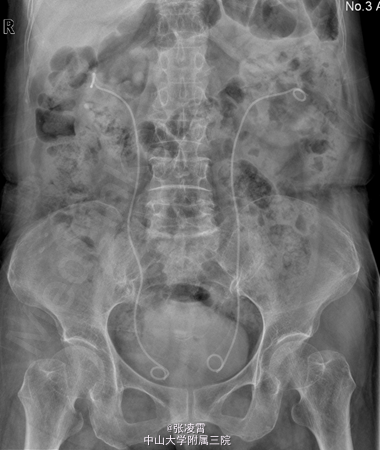

当地医院B超提示:肾功能受损改变,右肾多发结石。 CTU:1、双肾多发结石,双肾轻~中度积液、炎症;双肾萎缩,双肾功能减低2、双肾多发囊肿3、腹主动脉、双侧髂动脉硬化 核素肾动静态显像:1、右肾灌注、功能中度受损,右上尿路不完全性梗阻可能性大。2、左肾灌注、功能中度受损。 肌酐:281.000umol/L 尿素氮:14.220mmol/L 尿常规:白细胞计数 28.1个/ul

诊断:1.双肾结石 ;2.泌尿道感染;3.肾功能不全 经完善相关术前检查,予行双侧输尿管软镜下碎石术。手术耗时约3小时,手术顺利,出血约5ml。

此患者双侧肾功能都不是很好,入院前有双侧腰腹部疼痛的情况,并且有尿路感染,考虑还是结石导致的感染。患者进行ECT检测发现左侧GFR为23.93,右侧为14.69。一般来说GFR小于10可以考虑直接行肾切手术。该患者还没有做肾切的指征,并且双侧肾结石都不大,行经皮肾镜对肾脏损害较大,综合考虑做输尿管软镜应为最佳手术方式。